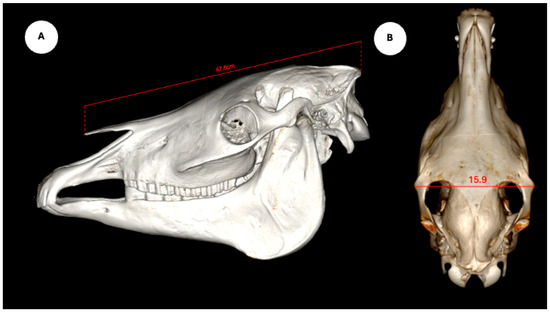

The study also evaluated cranial dimensions by measuring skull length—from the occipital protuberance to the rostral border of the nasal bone (Figure 6A)—and zygomatic width, defined as the distance between zygomatic bone borders (Figure 6B) [12].

Figure 6.

Volume rendered images of the equine skull showing (A) skull length, measured from the external occipital protuberance to the rostral border of the nasal bone, and (B) skull width, measured between the lateral edges of the zygomatic arches.

3. Results

Descriptive statistics for the study population are summarized as follows. Regarding breed distribution, 20 animals (95.23%) were crossbred, and one (4.76%) was a pure English Horse. In terms of sex, 18 individuals (85.71%) were male and 3 (14.29%) were female. The average body weight was 467.54 ± 34.94 kg (range: 400–530 kg), and the mean age was 17.00 ± 4.99 years (range: 10–25 years). Regarding head measurements, the mean nasal–occipital length was 47.80 ± 2.00 cm (range: 46.5–53.0 cm), and the mean zygomatic width was 17.15 ± 1.25 cm (range: 16.0–20.0 cm).

In contrast, our study assessed the relationship between ocular anatomy and cranial morphometrics—specifically nasal–occipital length and zygomatic width—thus providing a skeletal-based morphometric perspective. Interestingly, although the correlations between skull dimensions and certain intraocular structures (such as lens height and posterior chamber width) were weak, they were statistically significant. These findings align with other investigation conducted in horses [5], where lens length did not correlate significantly with skull dimensions or other ocular parameters. By contrast, we identified strong internal correlations among lens dimensions (height and width), which may have practical implications for surgical planning and prosthetic design. Overall, our results suggest that cranial morphology exerts subtle but measurables influences on ocular anatomy, highlighting the need for further investigations with larger and more diverse populations to validate and expand these preliminary associations.

Although the statistically significant associations observed between skull dimensions (nasal–occipital length and zygomatic width) and certain intraocular parameters (e.g., lens height, posterior chamber width) were weak, they suggest that cranial morphology may exert subtle influences on ocular anatomy. Consistent with findings in other species with limited visual acuity, these weak correlations suggest that external morphometry alone is insufficient to accurately predict intraocular measurements.